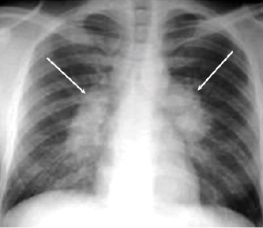

5. Hilar or mediastinal lymphadenopathy (bihilar lymphadenopathy) - Enlargement of lymph nodes in one or both hila or within the mediastinum, with or without associated atelectasis or consolidation.